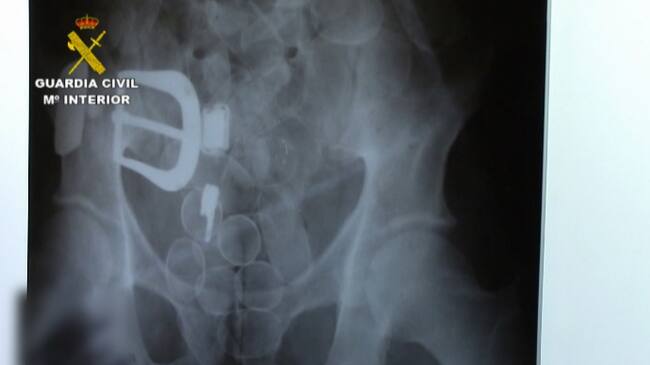

Radiografía de la droga oculta en el cádaver del "mulero" asesinado(CADENA SER)

Un kilo de cocaína en el estómago

Como resultado de la investigación y según se desprendió del resultado de la autopsia, J.A.U.I., falleció por una obstrucción intestinal causada por la gran cantidad de "bellotas" de cocaína que había ingerido, ya que se estima que podría haber alojado en su estómago alrededor de un kilogramo de esta sustancia estupefaciente.

En el cadáver no se hallaron bellotas o restos de droga de una posible rotura de alguna de las bolas de cocaína. Sin embargo, se encontraron restos de analgésicos, que posiblemente le facilitó la organización para mitigar el dolor que tuvo que sufrir hasta que falleció.